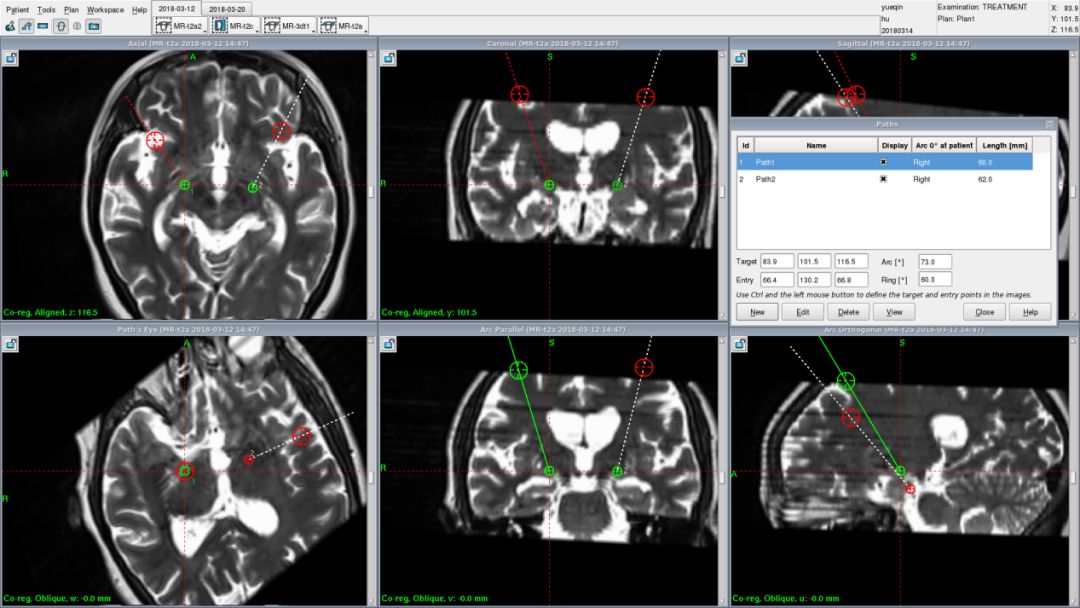

患者有家族史,基因检查显示为亨廷顿病。MRI检查显示双侧尾状核、壳核明显明显萎缩。

患者行双侧GPI DBS手术,手术顺利。下图为患者的计划,该患者大脑皮层萎缩明显、对称性尾状核萎缩,侧脑室前脚尾状核区呈球形向外膨起,呈“蝴蝶征”。这类型的患者对靶点的要求十分高,精确的确定靶点,对于术后的效果可以起到更好的作用。

开机3天后,患者的UHDRS运动评分改善37%,目前,术后患者的运动功能得到了部分改善,智力等没有进展性的下降,基本可以生活自理。综合近几年的一些相关文献,Gpi DBS能够部分改善亨廷顿病患者的运动症状,对于高级皮层功能受累较轻的患者可以延长患者生活自理的时间,提高生活质量。对于尝试使用DBS治疗亨廷顿舞蹈病的患者,一定要把握好适应症。在临床医生向患者提出DBS治疗HD之前,仍然应该对该技术疗效进行深入探索。